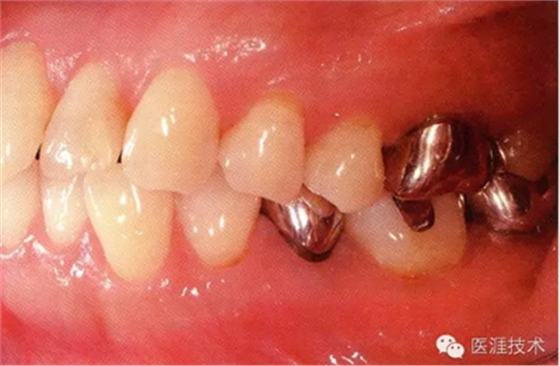

55歲牙周炎男性的臨床照片

55歲男性抽煙患者(1天20支、抽煙35年)。菌斑控制得不好。通過牙周探診,全頜有4~9mm的牙周袋,有1~3度的根分叉部病變。通過X光片觀察,上頜前牙中度牙槽骨吸收,其他地方有中度牙槽骨吸收。受吸煙影響,牙齦纖維性肥厚,呈紅黑色。牙齦幾乎沒有浮腫和發(fā)紅,所以這個病例是從外觀上無法預(yù)測病癥嚴重程度的病例。